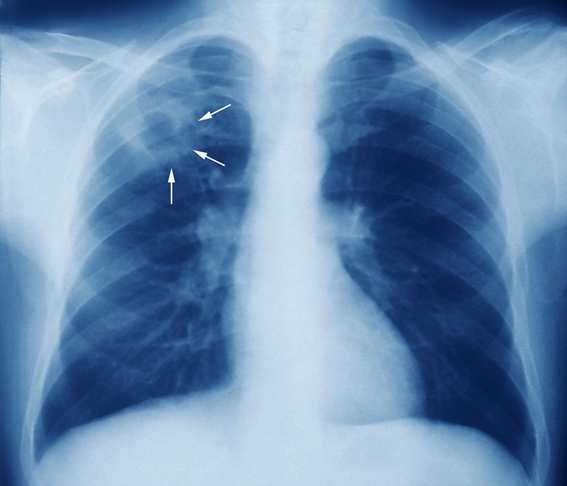

Como identificar a tuberculose no raio-x?

O diagnóstico por imagem é iniciado por avaliação do Raio-X, que deve ser solicitado para todo paciente com suspeita clínica de Tuberculose Pulmonar após a anamnese e exame físico. Essa solicitação tem por objetivo fazer a exclusão de outros diagnósticos diferenciais, avaliar a extensão do acometimento da doença e acompanhar a evolução do tratamento. Alguns achados suspeitos de no Raio-X são as cavidades, nódulos, consolidações, massas, derrame pleural e alargamento do mediastino.